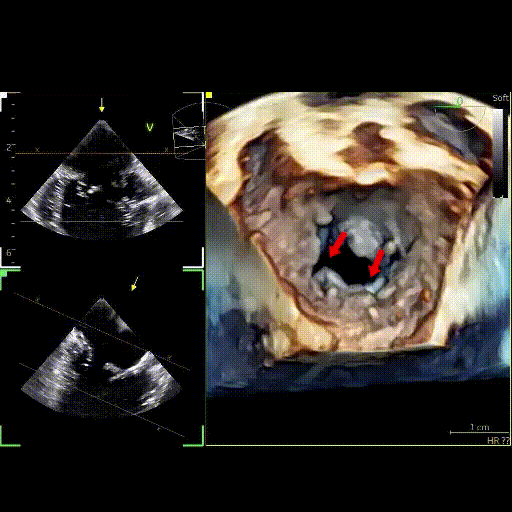

경식도 심장초음파(TEE)를

활용한 판막 교정

경식도 심장초음파(TEE, Transesophageal Echocardiography)는 이첨판의 손상 부위를 실시간으로 확인하고, 수술 중 정밀하게 교정하는 과정을 보여줍니다.

초음파를 통해 판막의 찢어진 부위(화살표 부분)를 직접 확인할 수 있으며, 이를 기반으로 정확한 봉합과 판막 성형술을 시행해 수술 후 판막의 정상적인 닫힘 기능을 복원할 수 있습니다.

경식도 초음파 (4D영상)